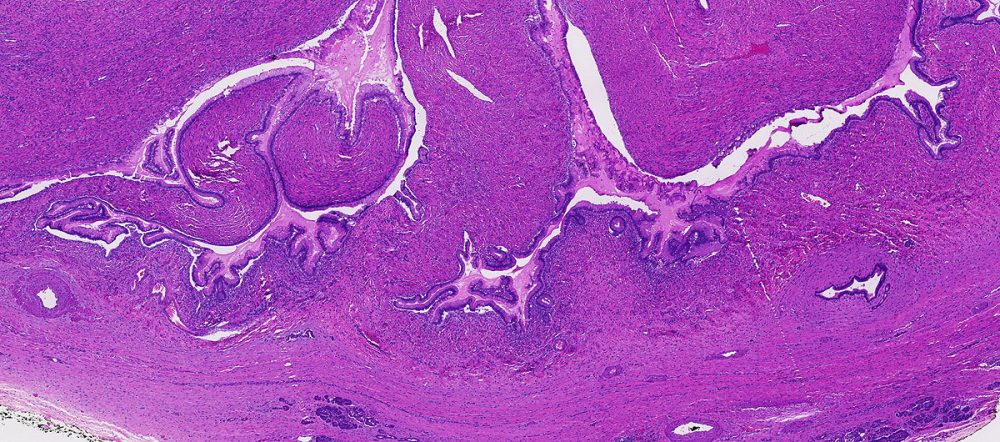

A term used to describe certain tumors which grow in finger-like projections. Pathologists use this term to describe some precancerous lesions in the pancreas (intraductal papillary mucinous neoplasm).

A benign (non-cancerous) tumor made up of cells that form glands (collections of cells surrounding an empty space).

The form of cancer that most people are talking about when they refer to "cancer of the pancreas." These tumors account for 75% of all pancreas cancers.

Microscopically, adenocarcinomas form glands. These tumors can grow large enough to invade nerves which can cause back pain. They also frequently spread (metastasize) to the liver or lymph nodes. If this happens the tumor may be considered unresectable.